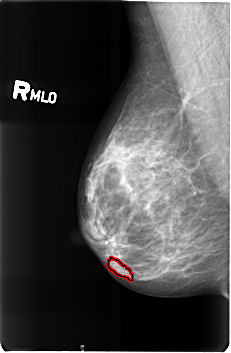

B_3360_1.RIGHT_MLO

RIGHT_MLO LINES 4584 PIXELS_PER_LINE 3000 BITS_PER_PIXEL 12 RESOLUTION 50 OVERLAY

FILE: B_3360_1.RIGHT_MLO.OVERLAY

TOTAL_ABNORMALITIES 1

ABNORMALITY 1

LESION_TYPE MASS SHAPE LOBULATED MARGINS CIRCUMSCRIBED

ASSESSMENT 4

SUBTLETY 3

PATHOLOGY BENIGN

TOTAL_OUTLINES 1

BOUNDARY